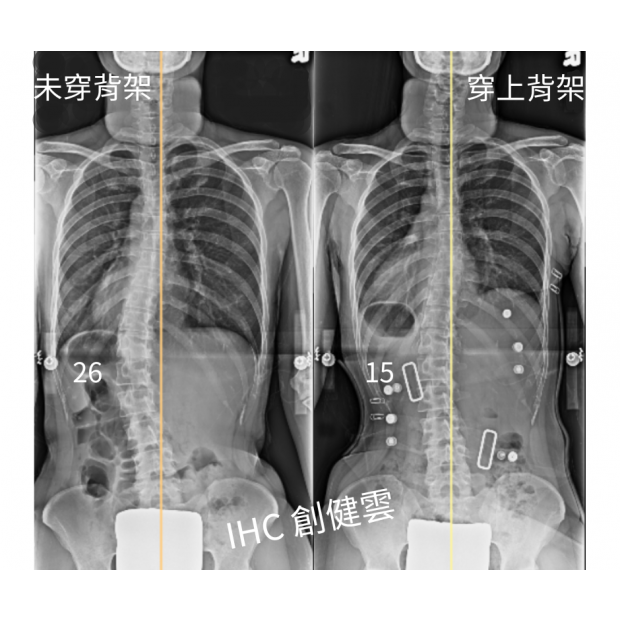

37歲脊椎側彎女生,腰彎26度